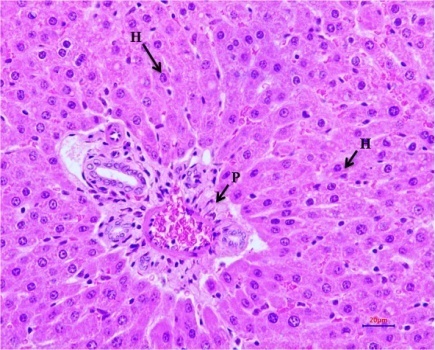

Fig. 12: Histopathological examination of experimental rat liver after 21 d treatment (HandE, 400 X magnifications). Liver section of (I) Normal control, (II)Diabetic control,(III)EOAM (EOFAE 250+AMLEAE250 mg/kg bw),(IV) EOAM (EOFAE 500+AMLEAE 250 mg/kg bw, Combination of (V)EOAM (EOFAE 500+AMLEAE250+Glib 5 mg/kg bw),(VI)EOAM (EOFAE 500+AMLEAE 250+Glib 5 mg/kg bw),(VII)Glibenclamide5 mg/kg bw.[Hepatocyte (HC), Normal Portal Triad (P), Hepatocellular Vacuolation (V), Portal Triad (P) and Hepatocyte (H)]

Histopathological studies

Histopathological examination of the experimental rat liver after 21 d treatment indicates that the liver section of normal control rats (NC) did not revealed any lesion of pathological significance as shown in fig. 12 (I). Liver section of diabetic control rat showed multifocal moderate hepatocellular vacuolation (microvesicular) as shown in fig. 12 (II). Liver section of diabetes-induced rats treated with low dose and high dose did not revealed any lesion of pathological significance as shown in fig. 12 (III) and (IV). Combination of low dose and high dose with glibenclamide also did not revealed any lesion of pathological significance as shown in fig. 12 (V) and (VI). Standard drug did not revealed any lesion of pathological significance as shown in fig. 12 (VII). Histopathology of the liver of STZ induced diabetic animals showed that there were hepatic changes, mild portal inflammation and hepatocellular vacuolation. After treatment of the animals by EOAM and glibenclamide, there was normal histology and reduced severity of the histopathological changes caused by STZ. The present study shows that the EOAM treated group III have significant antioxidant and antidiabetic activity as compare to diabetic control STZ induced animals. Equiproportion combination of both extracts shows significantly decreased in oxidative stress as evidenced by improved activities of antioxidant enzymes like superoxide dismutase, reduced glutathione. From the histological studies the liver section of group V and VI may have some interactions and liver section of diabetes-induced rats groups III, IV treated with EOAM and VII treated with well known sulfonylurea drugs like glibenclamide did not revealed any lesion of pathological significance, where the group III shows good significant effect (p<0.001) as compare to STZ-induced diabetic rats.